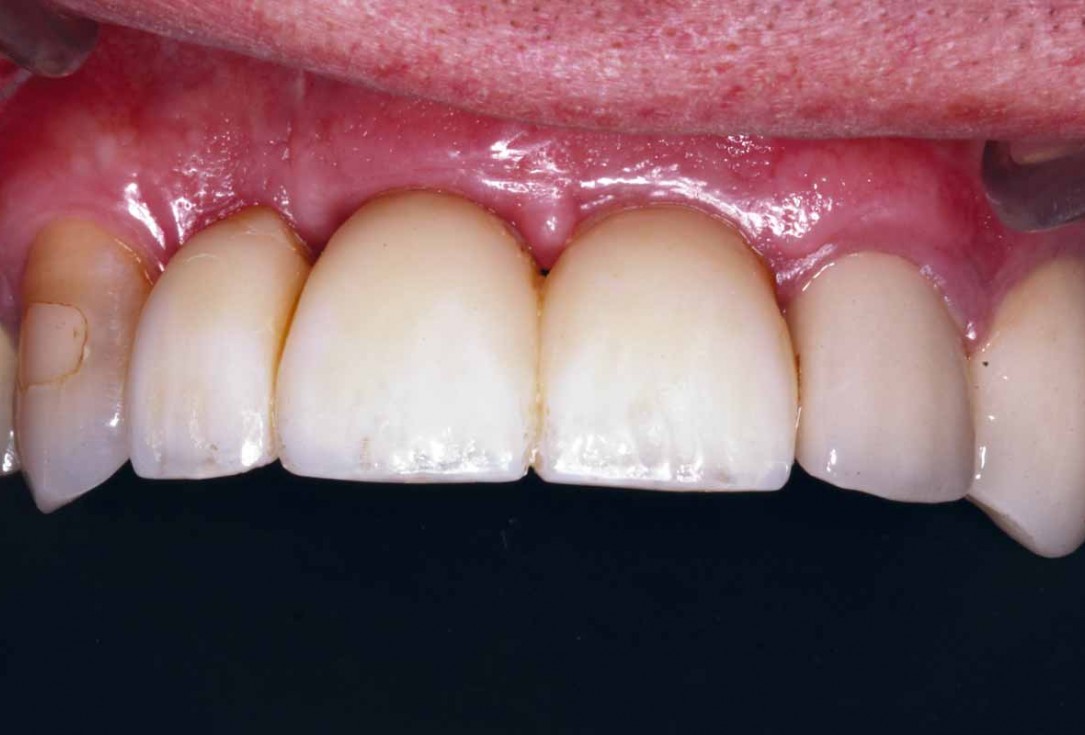

27/27 - Final clinical outcome

GBR and soft tissue augmentation with cerabone® and mucoderm® - H. Maghaireh & V. Ivancheva